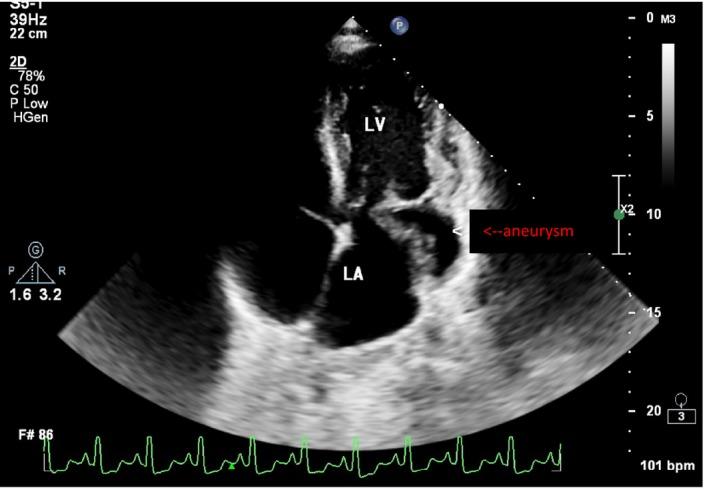

Submitral valve aneurysm in Bulawayo, Zimbabwe: A case report.

Submitral valve aneurysms are a rare but well-known pathology. These aneurysms should be considered as a differential diagnosis in young individuals who present with symptoms of heart failure and mitral regurgitation.